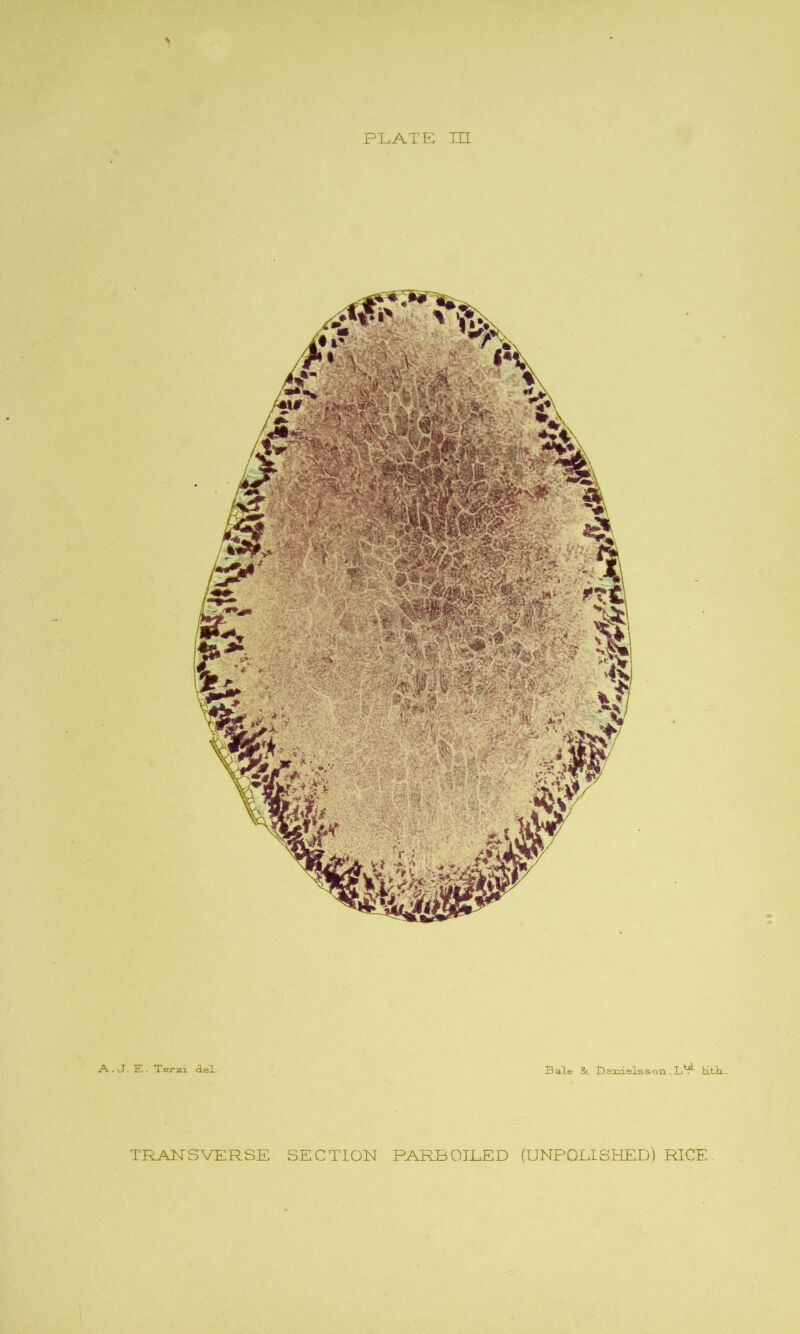

An inquiry concerning the etiology of beri-beri / by Henry Fraser and A.T. Stanton.

Credit: An inquiry concerning the etiology of beri-beri / by Henry Fraser and A.T. Stanton. Source: Wellcome Collection.